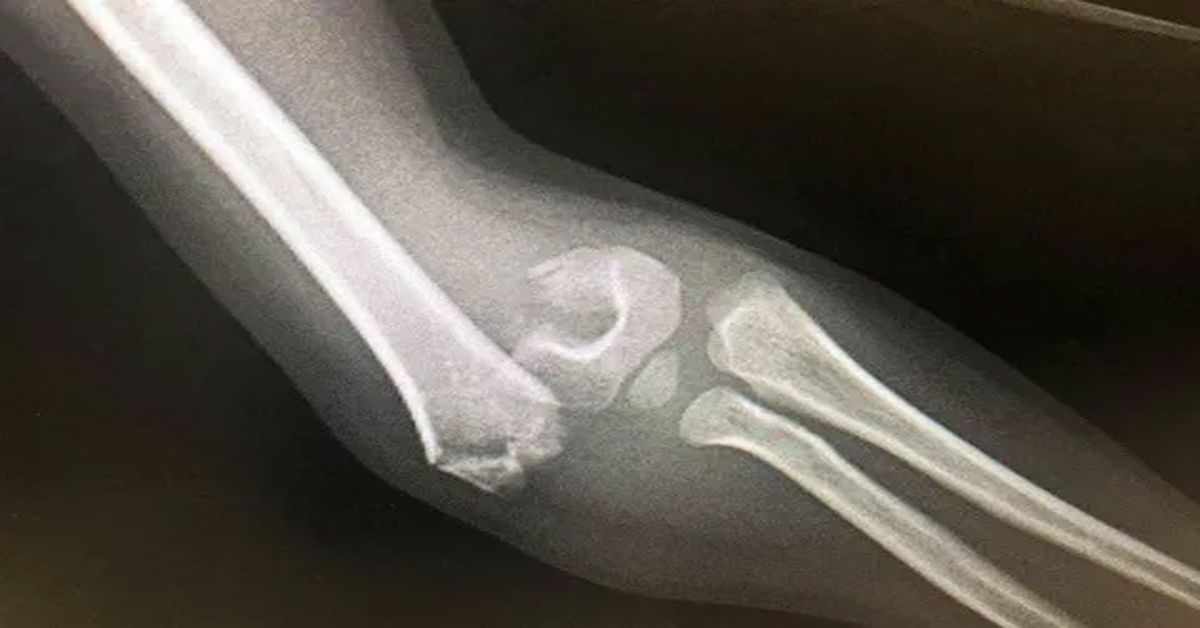

Hastalığın belirtileri arasında tekrarlayan kemik kırıkları, boy kısalığı, eğri kemikler ve bazen diş sorunları yer alır. Özellikle çocukluk ve ergenlik döneminde bu belirtiler daha belirgin hale gelir. Aileler, sık kırık yaşayan çocuklarda dikkatli olmalı ve düzenli kontrolleri aksatmamalıdır.

Kemik kırıkları sıklaşıyor, deformiteler artıyor veya hareket kısıtlılığı başlıyorsa cam kemik hastalığı tedavisi uygulanır. Tedavi, kemik yoğunluğunu artırmayı ve kırıkları önlemeyi amaçlar. İlaç tedavisi, fizik tedavi ve gerekirse cerrahi yöntemler tedavi planının temel unsurlarıdır. Hastanın yaşı, kırık geçmişi ve genel sağlık durumu dikkate alınarak kişiye özel bir plan hazırlanır.

Fizik tedavi, kasları güçlendirmek ve eklem hareket açıklığını artırmak için uygulanır. Egzersizler, hastaların günlük yaşamda daha güvenli hareket etmesini sağlar. Ayrıca düşme ve travmalara karşı koruma sağlayarak kırık riskini azaltır. Gerekli durumlarda cerrahi müdahale planlanır. Bu müdahale, kırıkların onarımı veya kemik deformitelerinin düzeltilmesi için yapılır.